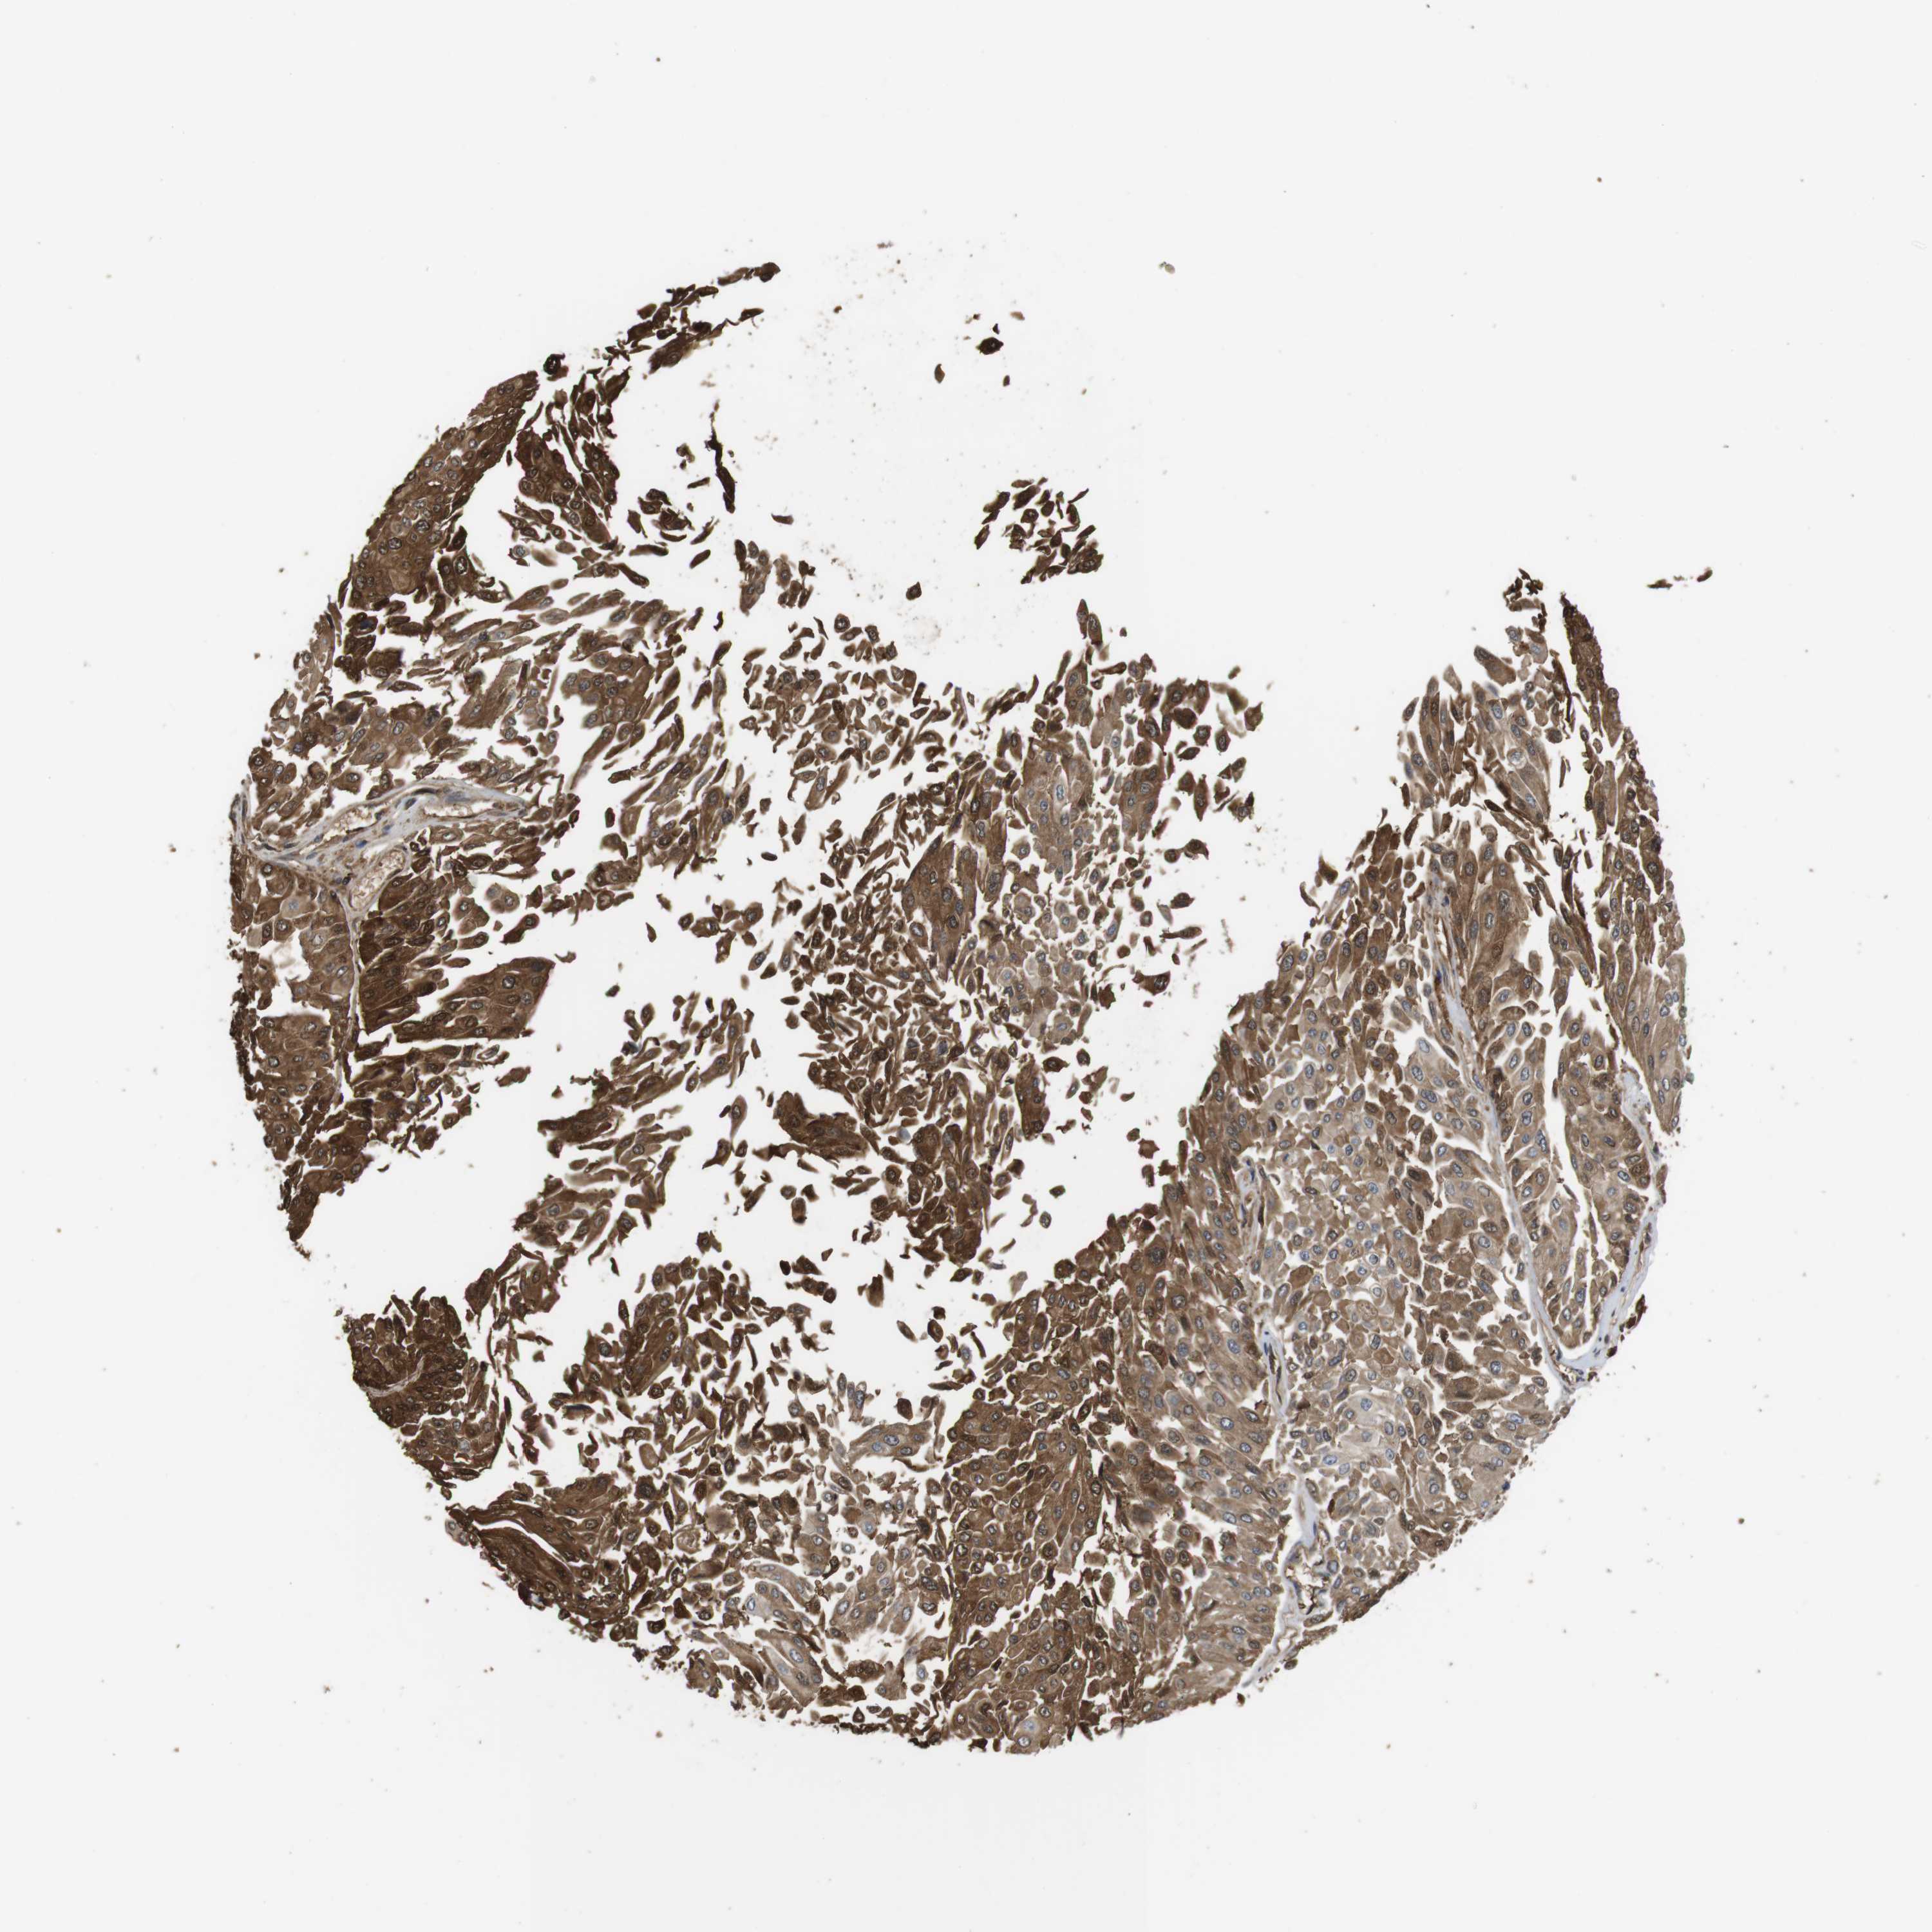

UROTHELIAL CANCER - Protein expressioni

A mouse-over function shows sample information and annotation data. Click on an image to view it in a full screen mode. Samples can be filtered based on level of antibody staining by selecting one or several of the following categories: high, medium, low and not detected. The assay and annotation is described here.

Note that samples used for immunohistochemistry by the Human Protein Atlas do not correspond to samples in the TCGA dataset.

Antibody stainingi

Antibody staining in the annotated cell types in the current human tissue is reported as not detected, low, medium, or high, based on conventional immunohistochemistry profiling in selected tissues. This score is based on the combination of the staining intensity and fraction of stained cells.

Each image is clickable and will lead to virtual microscopy that enables deeper exploration of all samples and also displays staining intensity scores, fraction scores and subcellular localization as well as patient and tissue information for each sample.

Antibody CAB015336

Antibody CAB069404

Staining

High

Medium

Low

Not detected

Intensity

Strong

Moderate

Weak

Negative

Quantity

>75%

75%-25%

<25%

None

Location

Nuclear

Cytoplasmic/membranous

Cytoplasmic/membranous,nuclear

Urothelial carcinoma, Low grade

Urothelial carcinoma, High grade

Urothelial carcinoma, NOS